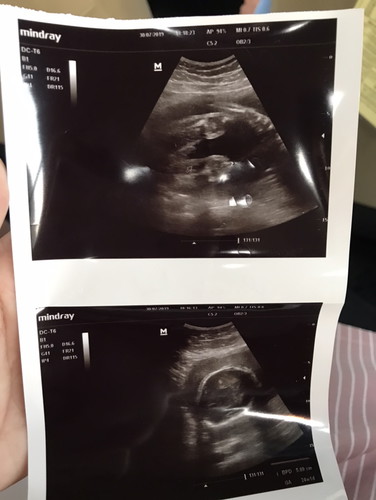

อยากรู้เพศไรค่ะ

สอบถามผู้รู้ หมอบอก ภาพแรกได้ เพศชาย หมออีกคนบอกภาพที่สอง ได้ เพศหญิง เปลี่ยนที่ซาว2ที่ อยากรู้ ได้เพศไรค่ะ

แอบยากค่ะ ภาพแรกเหมือนเห็นกระปู๋ แต่ก็ไม่มั่นใจว่าใช่มั้ย